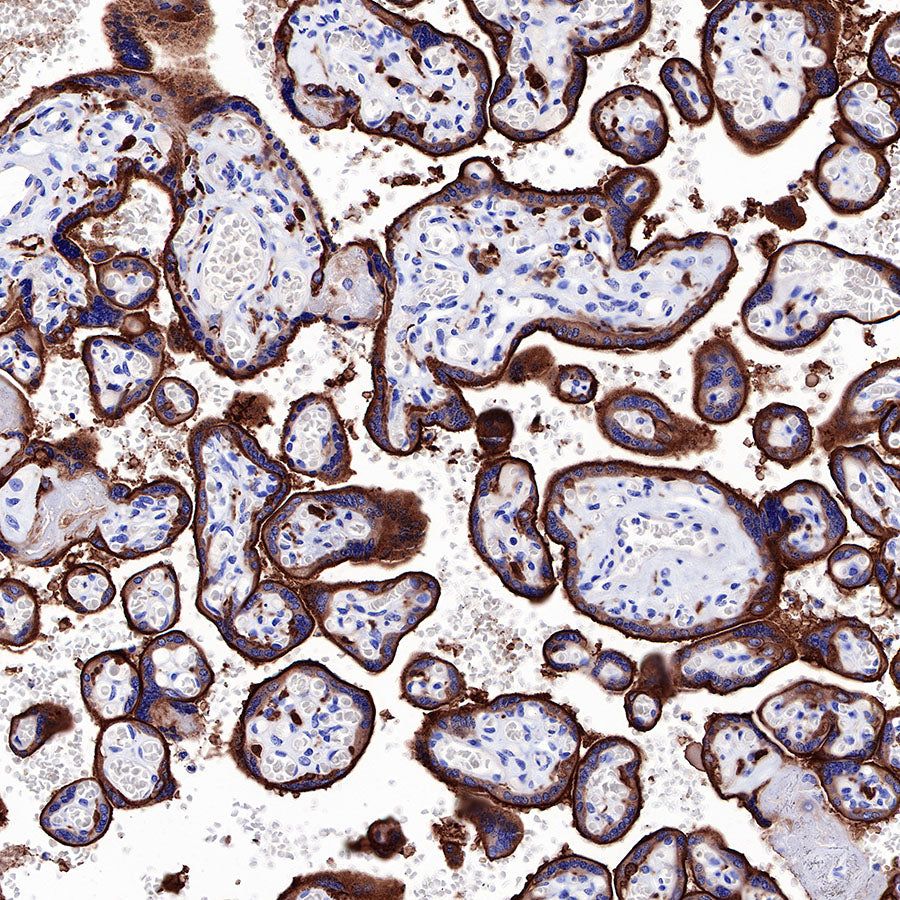

IHC shows positive staining in paraffin-embedded human placenta. Anti-EGFR antibody was used at 1/2000 dilution, followed by a HRP Polymer for Mouse & Rabbit IgG (ready to use). Counterstained with hematoxylin. Heat mediated antigen retrieval with Tris/EDTA buffer pH9.0 was performed before commencing with IHC staining protocol.